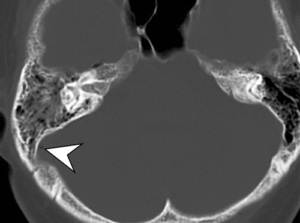

CT (computed tomography) scans are commonly used in the assessment of bone trauma due to their ability to provide detailed images of bones and surrounding